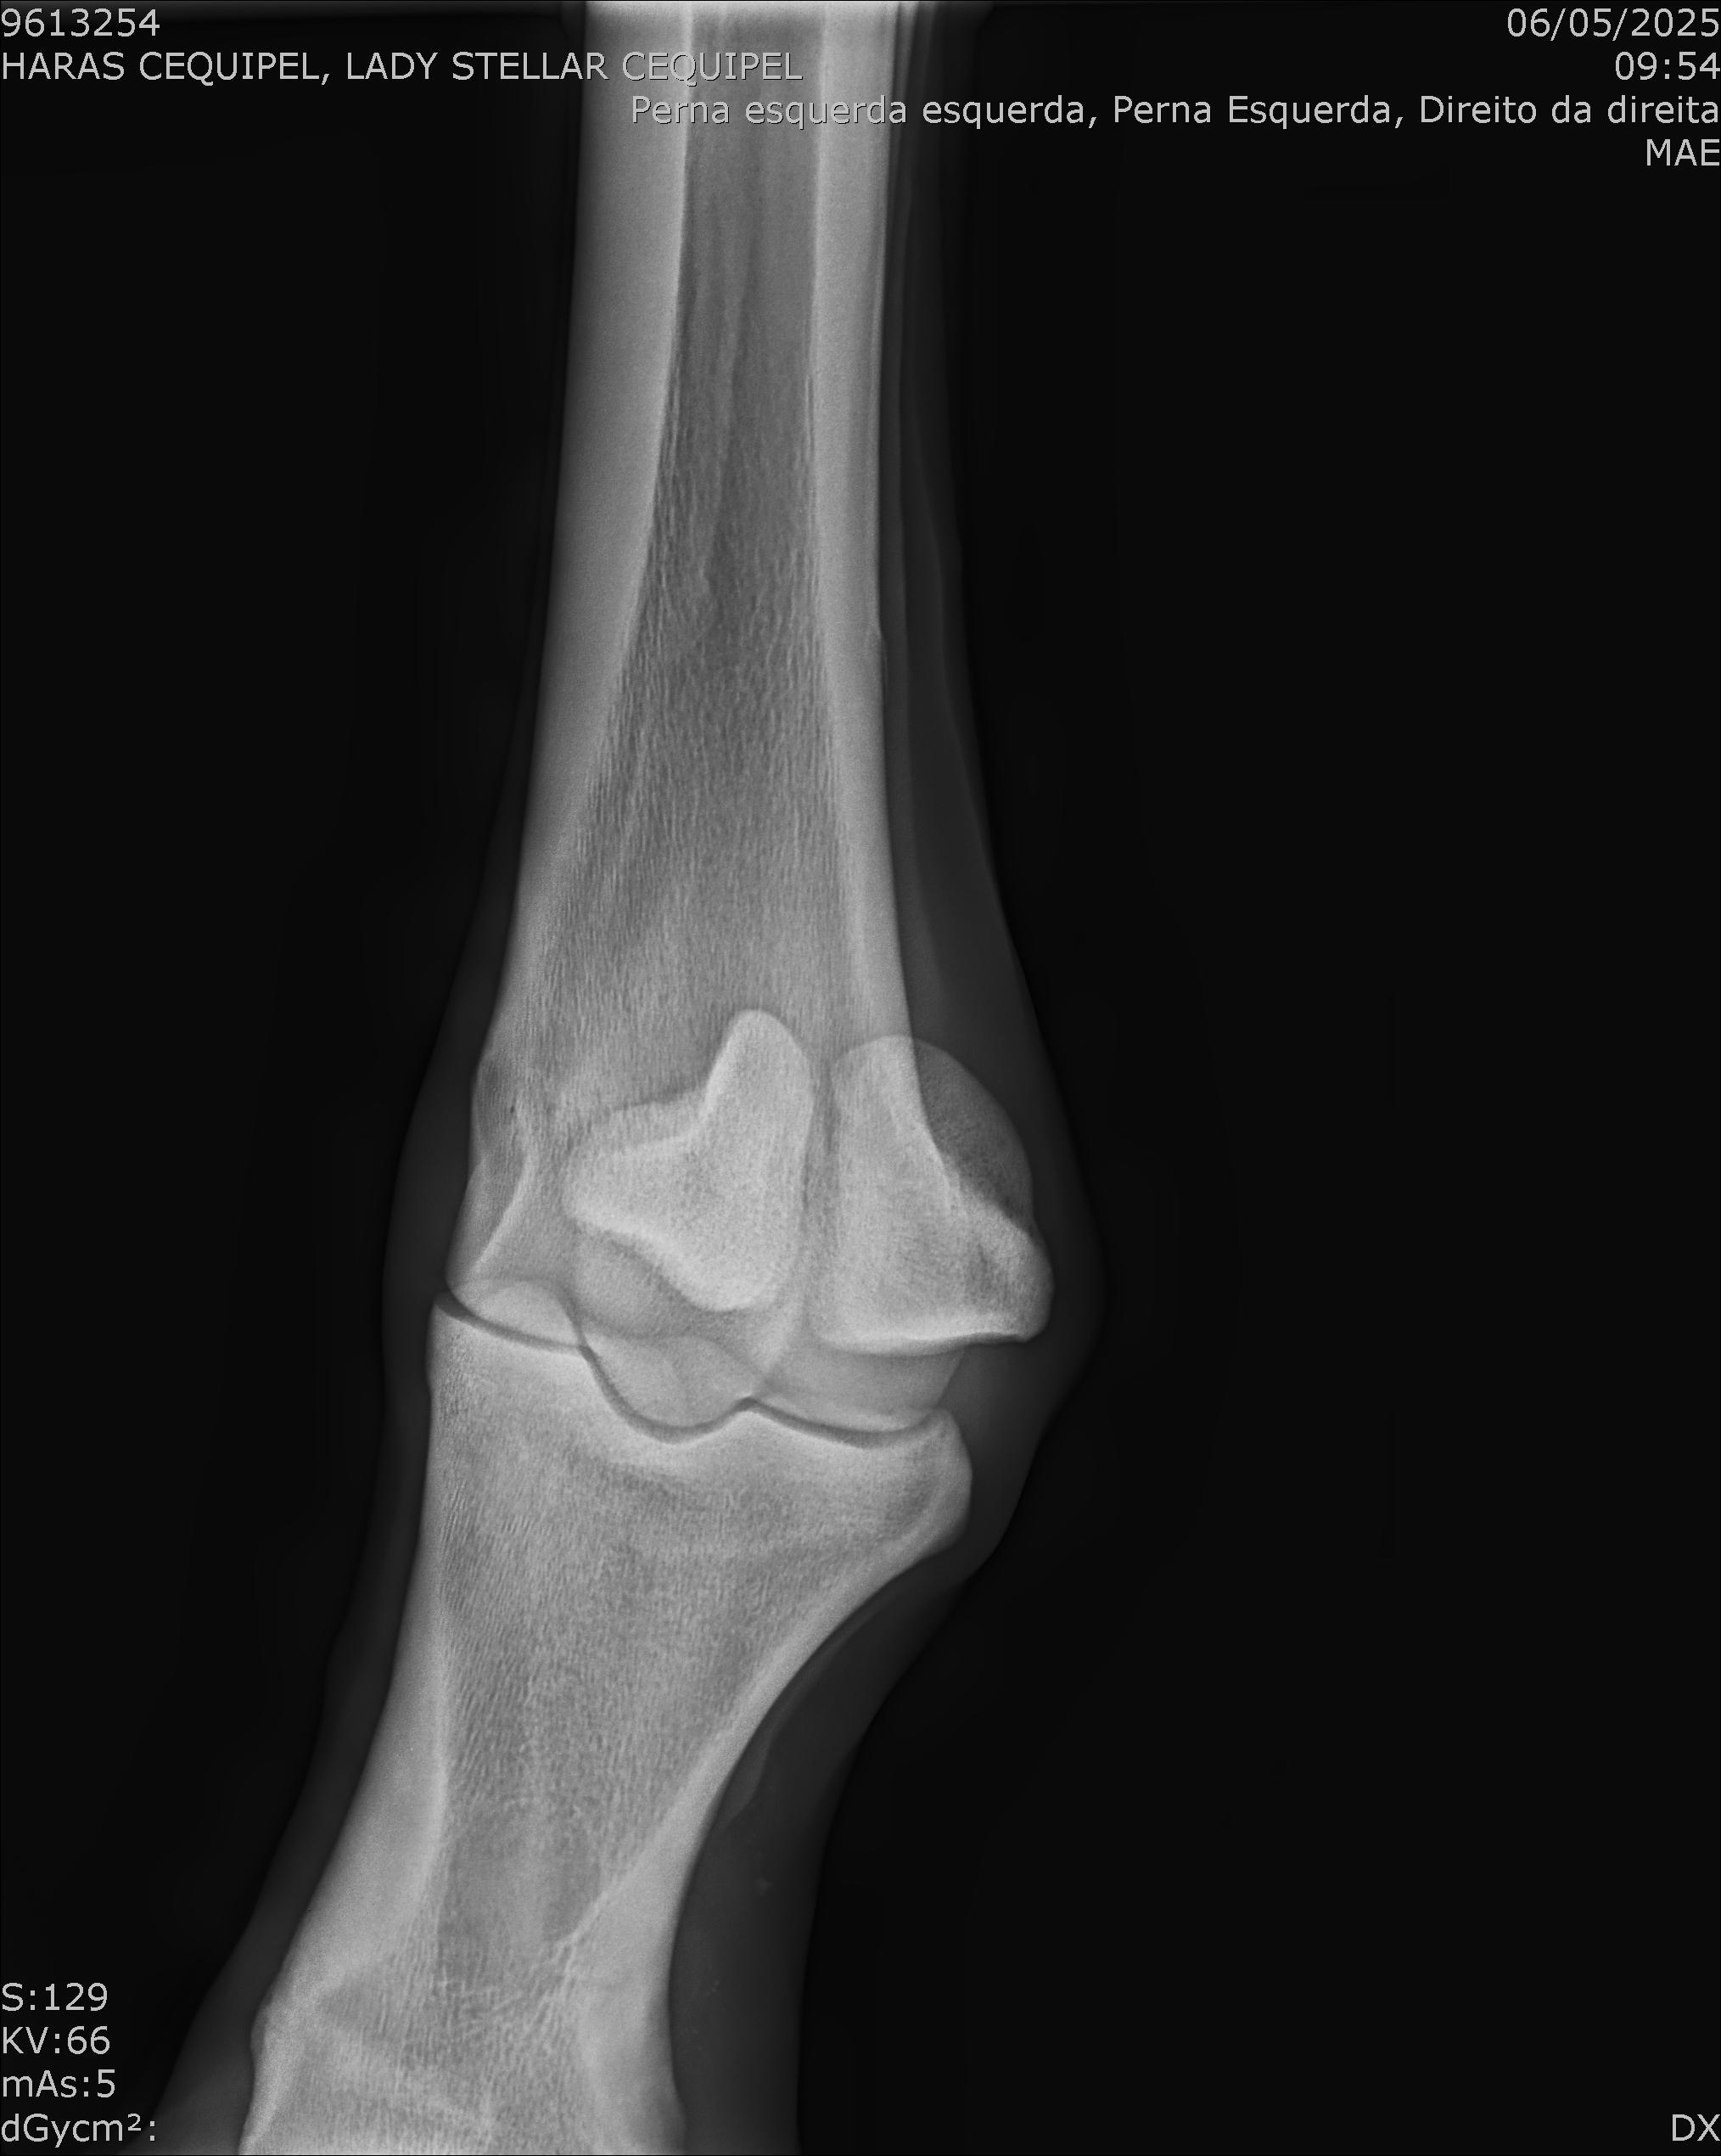

:: RAIOS-X DO LOTE